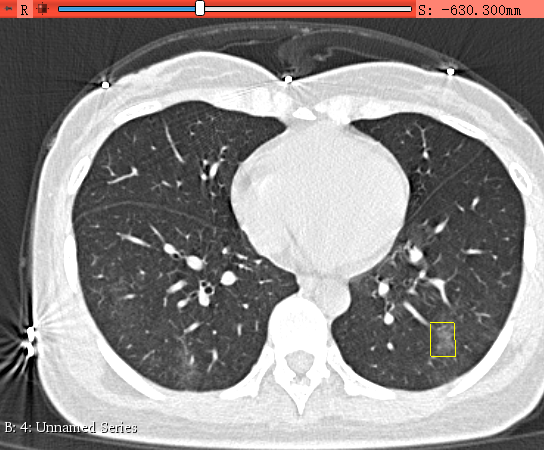

在横断面内,滚动鼠标浏览slice,找到有病灶的slice,可以通过前文链接里的那些交互操作方式改变窗宽窗位,或者放缩移动图像,来更加有效地查找病灶(注意有部分交互操作方式只有在None状态下才可以进行),例如下图的右下方有个病灶:

-

使用Draw工具,围绕着病灶左键点3-4个点,然后点击右键,生成一个比较扭曲的矩形包围住这个病灶就行了。

左键点了四个点: